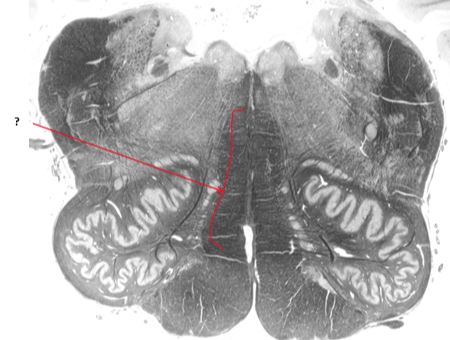

Name this and state its function.

Inferior olivary nucleus.

Name this, state its function, divisions and pathway.

Pyramidal tract.

Voluntary control.

Name this and state its function within its 2 parts.

Olive.

Inferior: integrates motor and sensory function

Superior: sound localisation.